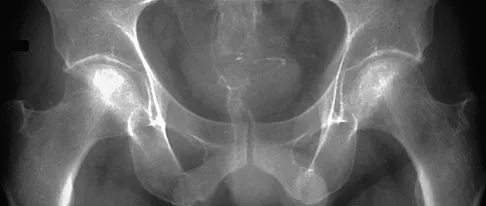

Figures 22a and 22b show the radiographs of a patient who reports stiffness of the hip and associated pain. Management should consist of

Explanation

The patient has grade IV heterotopic ossification with the limb in an abnormal nonfunctional position. Treatment should consist of excision of the bone to restore hip motion and prophylaxis to prevent recurrent formation. The best time to excise the bone is controversial, with no conclusive evidence supporting early or late excision. Pellegrini VD Jr, Koniski AA, Gastel JA, Rubin P, Evarts CM: Prevention of heterotopic ossification with irradiation after total hip arthroplasty: Radiation therapy with a single dose of eight hundred centigray administered to a limited field. J Bone Joint Surg Am 1992;74:186-200.